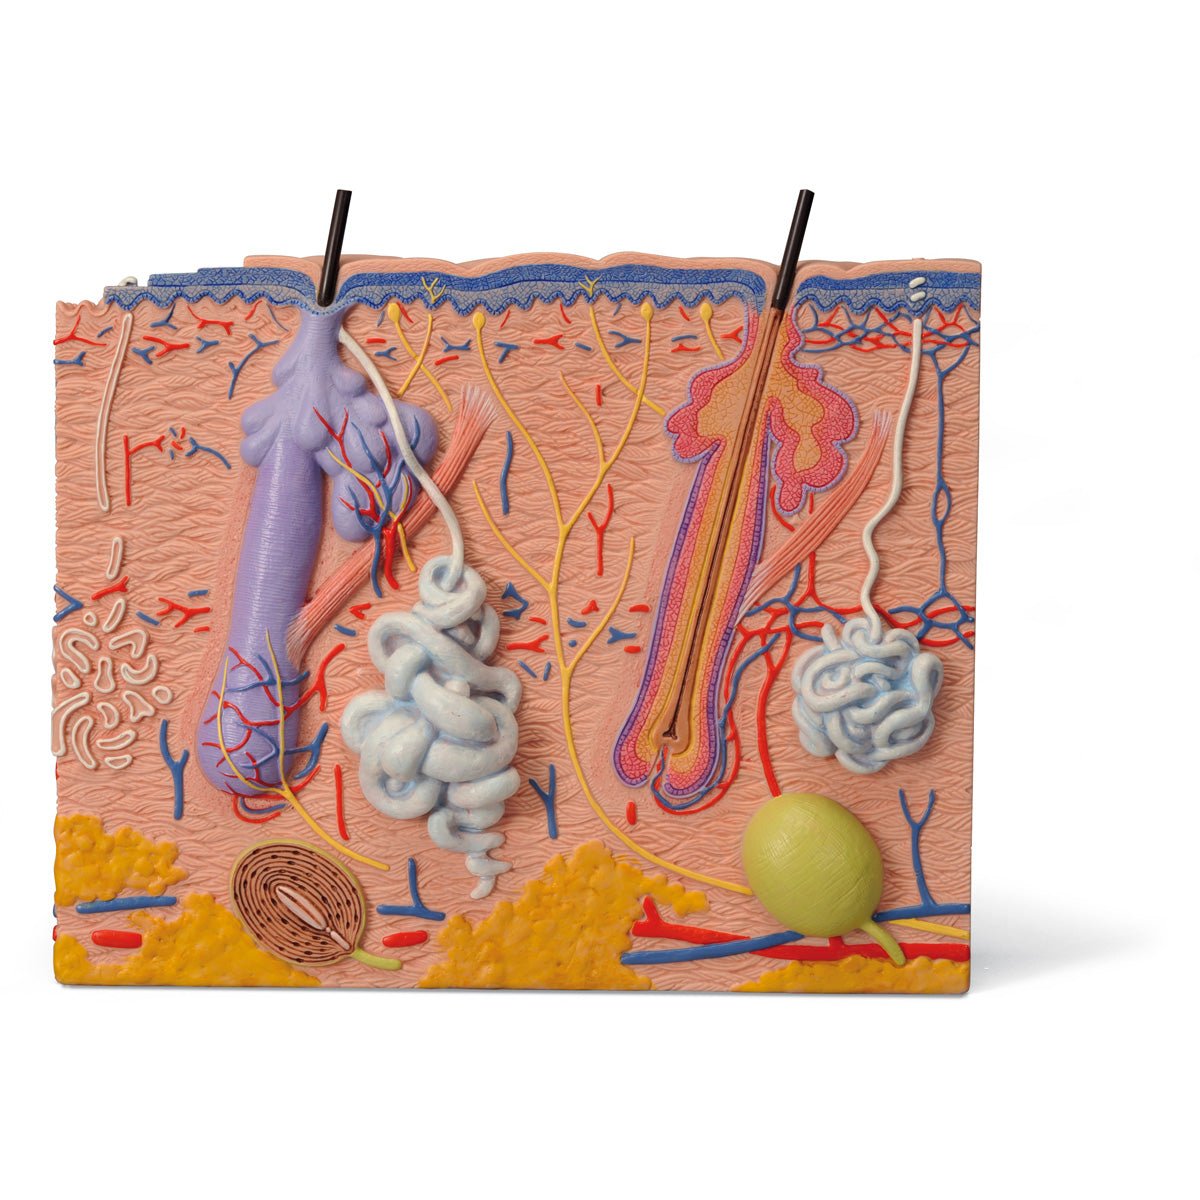

Salg af anatomiske modeller er det bærende element i eAnatomi, selvom vi også bruger mange ressourcer på at udvikle vores egne anatomiske materialer som fx plakater. Anatomiske modeller anvendes til forskellige formål og kan både vise afgrænset væv, organer samt organsystemer. Søger du en simpel model af knoglevæv eller måske en avanceret torso-model baseret på MRI teknologi, kan du finde det hele på eanatomi.com.